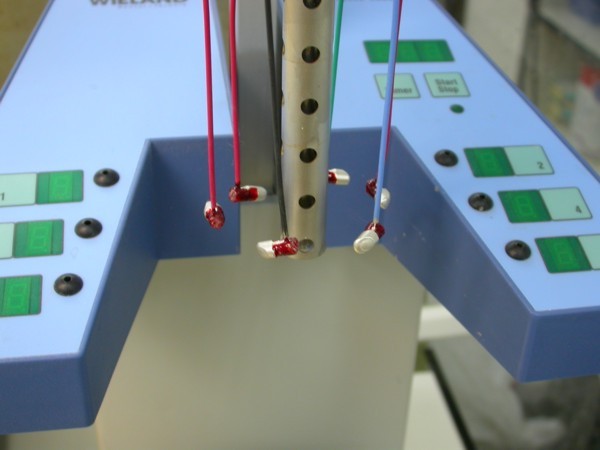

ABSTRACT La literatura oclusal se ha encargado de describir distintas funciones de la misma a través de los tiempos. El presente caso se realiza en forma de sobredentadura (over denture) debido a que la carencia de reborde óseo en el sector anterior verificado tanto clínicamente como mediante telerradiografía , impedía llevar a cabo una prótesis fija , por lo que se optó por un sistema de pilares ceramizados y paralelizados mediante el sistema SIRIUS, sobre seis implantes, y la conexión a una estructura de metal cerámica FIJA AMOVIBLE, mediante coronas telescópicas galvanizadas, otorgando al sistema la rehabilitación mediante una PIA(Prótesis Implanto Asistida con reposición ósea y gingival mediante porcelana rosa.) MATERIAL Y MÉTODOS: IMPLANTES:KLOCKNER SK-T.T.S. MONTAJE Y REGISTROS: ARCO FACIAL ESTÁTICO Y ARTICULADOR PRIMARIA: Abuttmets Ceramizados (I.P.S. D.SIGN IVOCLAR) SECUNDARIA: Cofias Galvanoformadas (AURO GALVAN CROWN WIELAND) TERCIARIA: Férula de Porcelana sobre Metal (I.P.S. D. SIGN IVOCLAR) CEMENTADO INTERFASE: NIMETIC CEM-ESPE DESARROLLO Se presenta el paciente a la consulta requiriendo la resolución de su maxilar inferior, el que se restaura mediante una férula de metal porcelana , en la que se preparan los lineamientos oclusales ideales (Spee-Wilson-Cuatro Niveles-etc) a fin de tener un sustrato de trabajo correcto, para la confección del maxilar superior, que porta una Prótesis Total convencional. Se estudia mediante Panorámica, Dentascan y Montaje en articulador semi ajustable. Se instalan seis implantes Klockner con Técnica Semisumergida pensados para una Carga diferida a tres meses después de la implantación Se realiza el arrastre de los Transfer mediante cubeta individualizada y fenestrada. Se confeccionan los abuttmentes correspondientes y se llevan a boca mediante una férula de posicionamiento realizada en Acrílico Duralay, el que por sus condiciones de carencia de cambios volumétricos verifican el correcto ajuste de los mismos Se ceramizan los abuttments y se paralelizan mediante el sistema SIRIUS, llevándolos a boca y chequeando su instalación Se confecciona una Prótesis Total Provisional que llevará el paciente durante el período de Osteointegración Se procede a la confección en laboratorio de las cofias galvánicas Sobre un nuevo modelo mayor se confecciona la férula de metal que uniremos en boca a las cofias galvanizadas mediante un cemento especial, una vez confeccionada la porcelana. Se prueba en boca la férula metálica, verificando su holgura que será ocupada por el cemento antedicho, y se comienza con el montaje de la cerámica y la verificación de los patrones oclusales de la misma. Se instala el todo haciendo morder al paciente con el medio cementante instalado. FIGURA 40 FIGURA 41 FIGURA 42 CONCLUSIONES La función de «GUIA CANINA», como esquema mas propicio para cumplir con los deseos de «autoprotección » de un SEG, rehabilitado o no, no se cumple al 100 % en casos como el presentado. La razones por las cuales el uso de la misma en lo que se da en denominar OCLUSIÓN MUTUAMENTE PROTEGIDA consiste en tres factores que detallo a continuación: A. En una función desoclusiva realizada por las piezas anteriores, como por ejemplo el canino, el BRAZO DE RESISTENCIA generado en la palanca desoclusiva, es por lo menos igual al brazo de potencia desarrollado, argumento de gran peso para hablar de la Desoclusión Canina como esquema de elección- B. La inclinación de los rebordes marginales del canino superior, esta dentro de los 70º, a diferencia de la tabla oclusal posterior que puede variar entre los 20 y 40 º. C. El estimulo que generan los dientes anteriores se dirige por via aferente al SNC, exitando por vía eferente, fundamentalmente al músculo temporal en sus fibras anteriores o VERTICALES…fibras de mucha menos capacidad de fuerza, que si la acción la ejercieran las fibras de la cincha PTERIGO MASETERINA, que serían exitadas en el caso de una Función de Grupo. EN EL CASO PRESENTADO LAS DOS PRIMERAS RAZONES TIENEN VIGENCIA. Sin embargo la última de ellas , al no tener los Implantes terminaciones nerviosas como las que posee el periodonto , los estímulos que llegan al SNC no se cumplen, y por lo tanto no existe la respuesta que por conducción eferente estimularía al músculo temporal a su acción. De la misma manera, el hecho que estos Implantes estén ferulizados , trasmite fuerzas laterales también a los posteriores, y no solo a los que actúan como caninos. El beneficio de las dos primeras razones de uso de una Función Canina en un caso como este, obedece a que de por si las mismas minimizan la acción direccional de las fuerzas, las que sin embargo son compartidas por las piezas posteriores tanto del LT como del LnT. En este compartir de la función, me resulta conveniente denominar a este esquema: FUNCIÓN DE GRUPO POSTERIOR DE ACCIÓN CANINA. ———————————————————————————————————- PIE DE FOTOS: 37: CASO TERMINADO